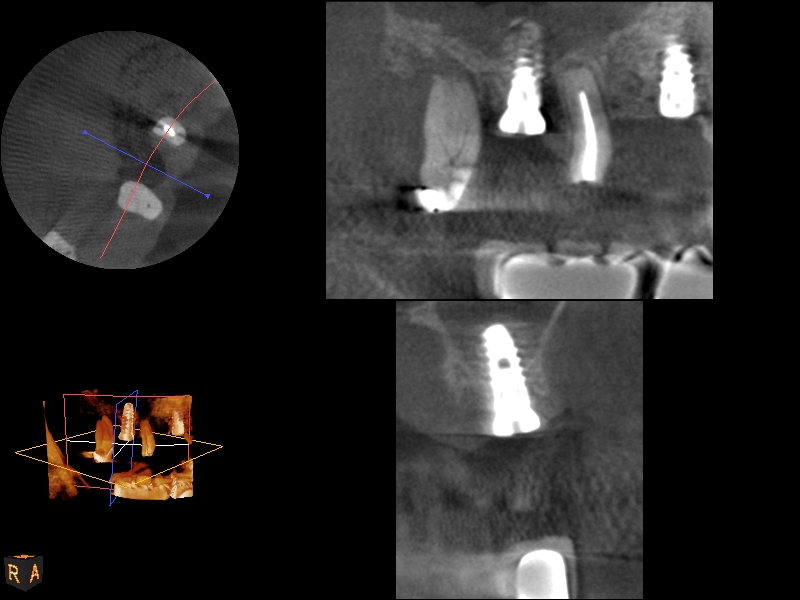

CBCT scan (Kodak 9000D) of implant No. 14 showing homogeneous appearance of the bone.

Fig. 19

A 74-year-old male patient presented with about 4 mm to 5 mm of native bone in the No. 4 position (Figure 17). A composite graft, as described in Case 1, was used, as was the same implant type, but the implant was 11.5 mm in length with a taper of 5 mm to 4.2 mm. The approximately 16-month post-healed floor of the sinus was raised about 7 mm to 8 mm (Figure 18). The CBCT scan taken at 16 months postoperatively showed no change in appearance from the area of the old floor of the sinus to the new bone formed (Figure 19). Although it was endodontically involved, tooth No. 15 was not extracted, against professional advice. As can be seen in Figure 18, the No. 14 implant is acting as a bridge abutment.

This patient was a 73-year-old man with only about 3.5 mm of native bone in the No. 3 site (Figure 20). The composite graft used here was a 50:50 mixture of DFDBA and deproteinized bovine bone mineral (Osteohealth, www.osteohealth.com) with approximately 40% calcium sulfate added. The implant was the same type and length as in Case 1 above. Figure 21 shows the area on the day of placement. In the CBCT scan on the day of placement (Figure 22), the native bone and bone graft were clearly discernable. However, the postoperative radiograph taken at 6.5 months (Figure 23) showed no marginal bone loss and a significantly denser appearance than when the graft was place. The membrane was raised about 7 mm to 8 mm. The final radiograph was taken after extraction of tooth No. 2 and after extraction of tooth No. 4 and immediate implant placement.